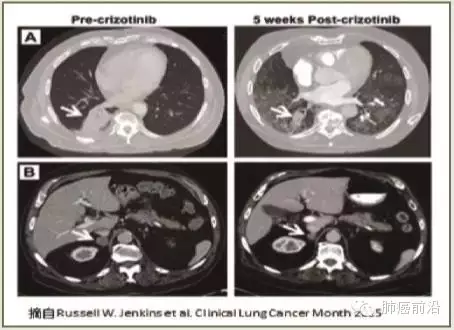

今年2月美国Dana-Farber癌症研究所报告了全球首例MET基因剪接点突变的晚期肺腺癌对克唑替尼有效(见图7)。该患者EGFR、KRAS、ALK、ROS1和RET等驱动癌基因均为阴性,但靶向二代测序(next generation sequencing, NGS)显示MET基因14号外显子剪接点突变(c.2887-18_2887-7del12),IHC提示50%癌细胞表现为磷酸化c-Met蛋白2+的阳性反应,与c-Met蛋白的活化状态相一致。最近肺腺癌全外显子测序的数据显示,MET基因14号外显子剪接点突变占了肺腺癌患者的4.3%,是MET基因扩增的两倍。尽管是个案报告,但隐藏的临床研发价值非常看好,临床靶向二代测序检测MET基因这种剪接点的突变,可能更有助于实现MET基因剪接点突变晚期肺腺癌患者的精准医学。